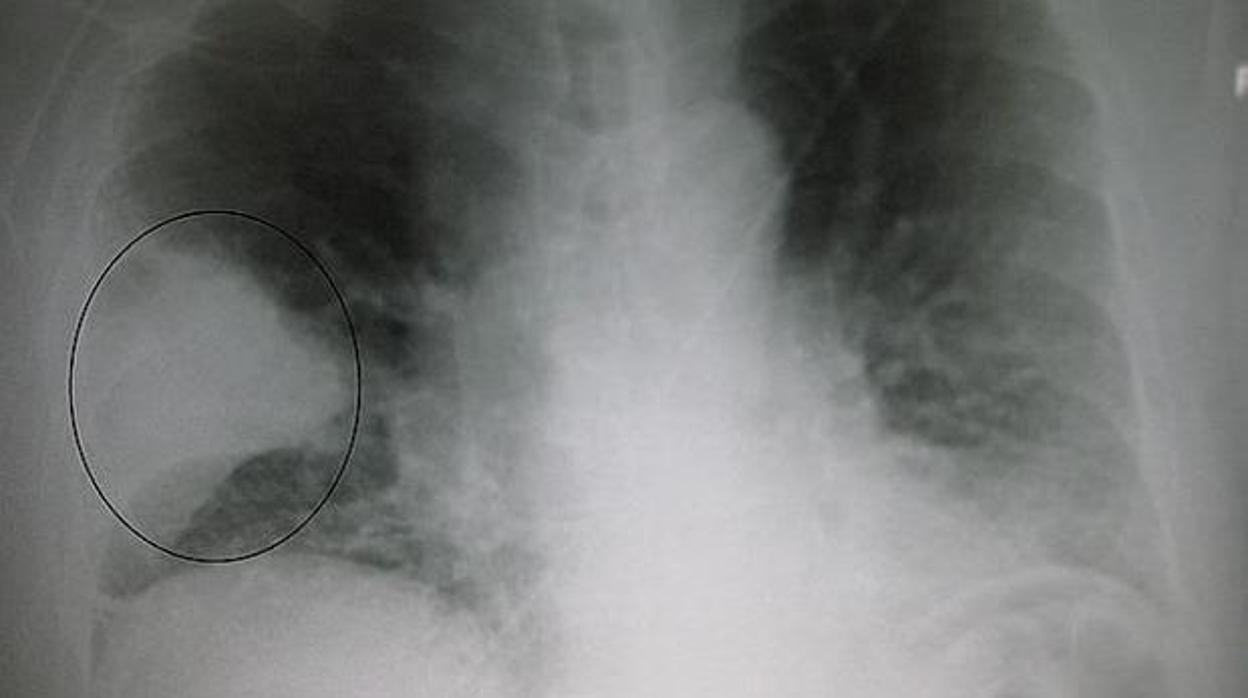

La mayoría de las personas respiran sin pensar. Los afectados por fibrosis quística solo piensan en respirar. Se trata de una de las enfermedades hereditarias más frecuentes causada por un gen defectuoso que lleva al cuerpo a producir un líquido anormalmente espeso ... y pegajoso. Este moco se acumula en las vías respiratorias de los pulmones, en el páncreas y ocasiona infecciones pulmonares potencialmente mortales además de serios problemas digestivos.